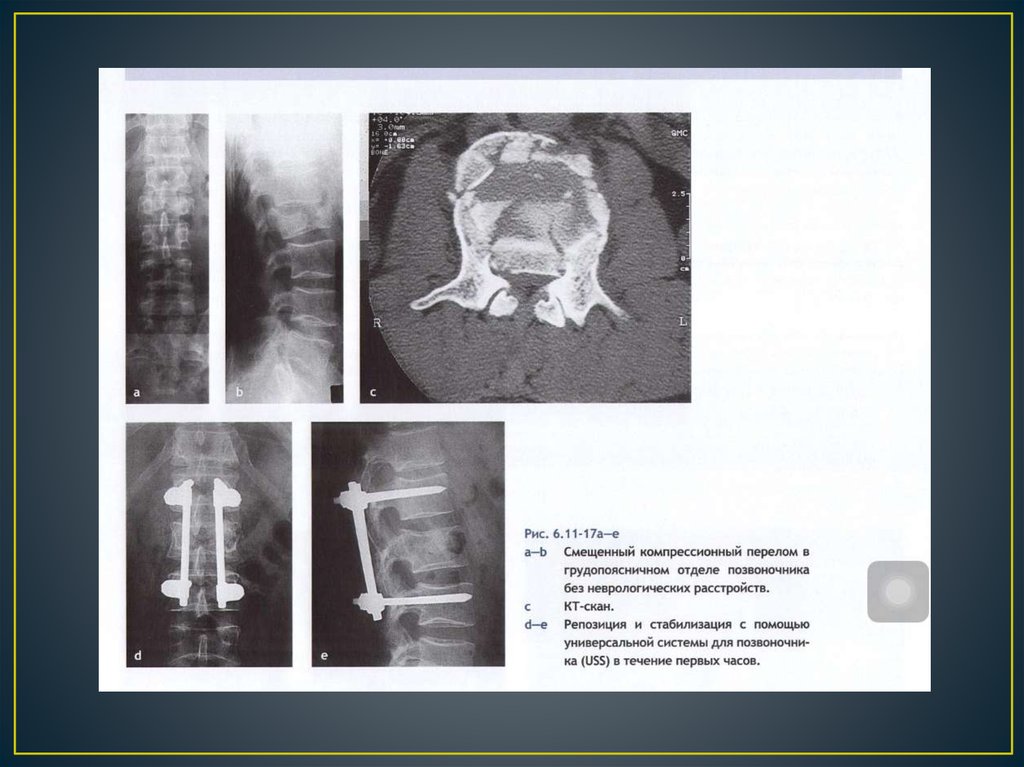

Позвоночно – спинальная травма